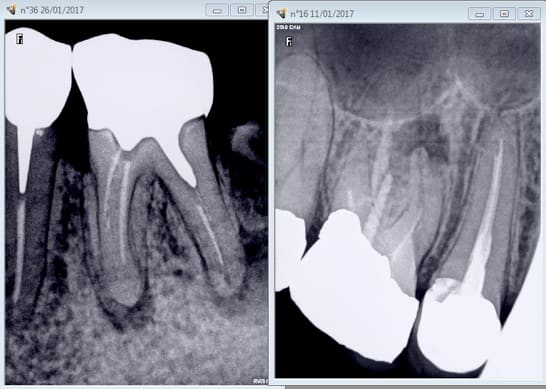

dans le cas de l'endo-couronne, qui n'est ni un onlay ni une couronne, je cote juste HN ?

sinon, pour aller dans le sens de GéPé, le "plateau" de l'endocouronne est évidemment ce qu'il y a de plus favorable mécaniquement dans le cas d'un assemblage collé.